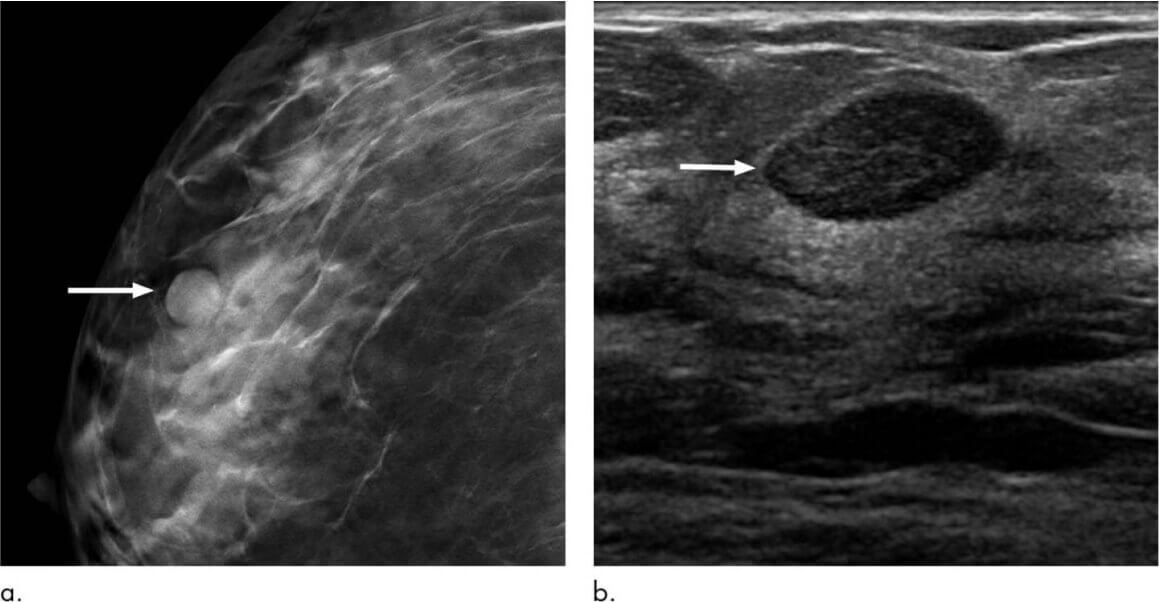

По результатам УЗИ и маммографии, выполненным 12 месяцев назад, выявлено очаговое образование, присвоена категория BI-RADS 3.

Рис. 2а/b — отмечается округлое новообразование неправильной формы с четкими контурами и гомогенной структурой, которое наиболее вероятно соответствует категории BI-RADS 3.

Врачом-онкологом пациентке было рекомендовано повторить обследование в прежнем объеме через 6 месяцев. Со слов больной, по причине семейных обстоятельств рекомендации не были соблюдены. Также пациентка на протяжении последнего года отмечала умеренный рост «этой непонятной шишки», однако к врачу повторно не обращалась.